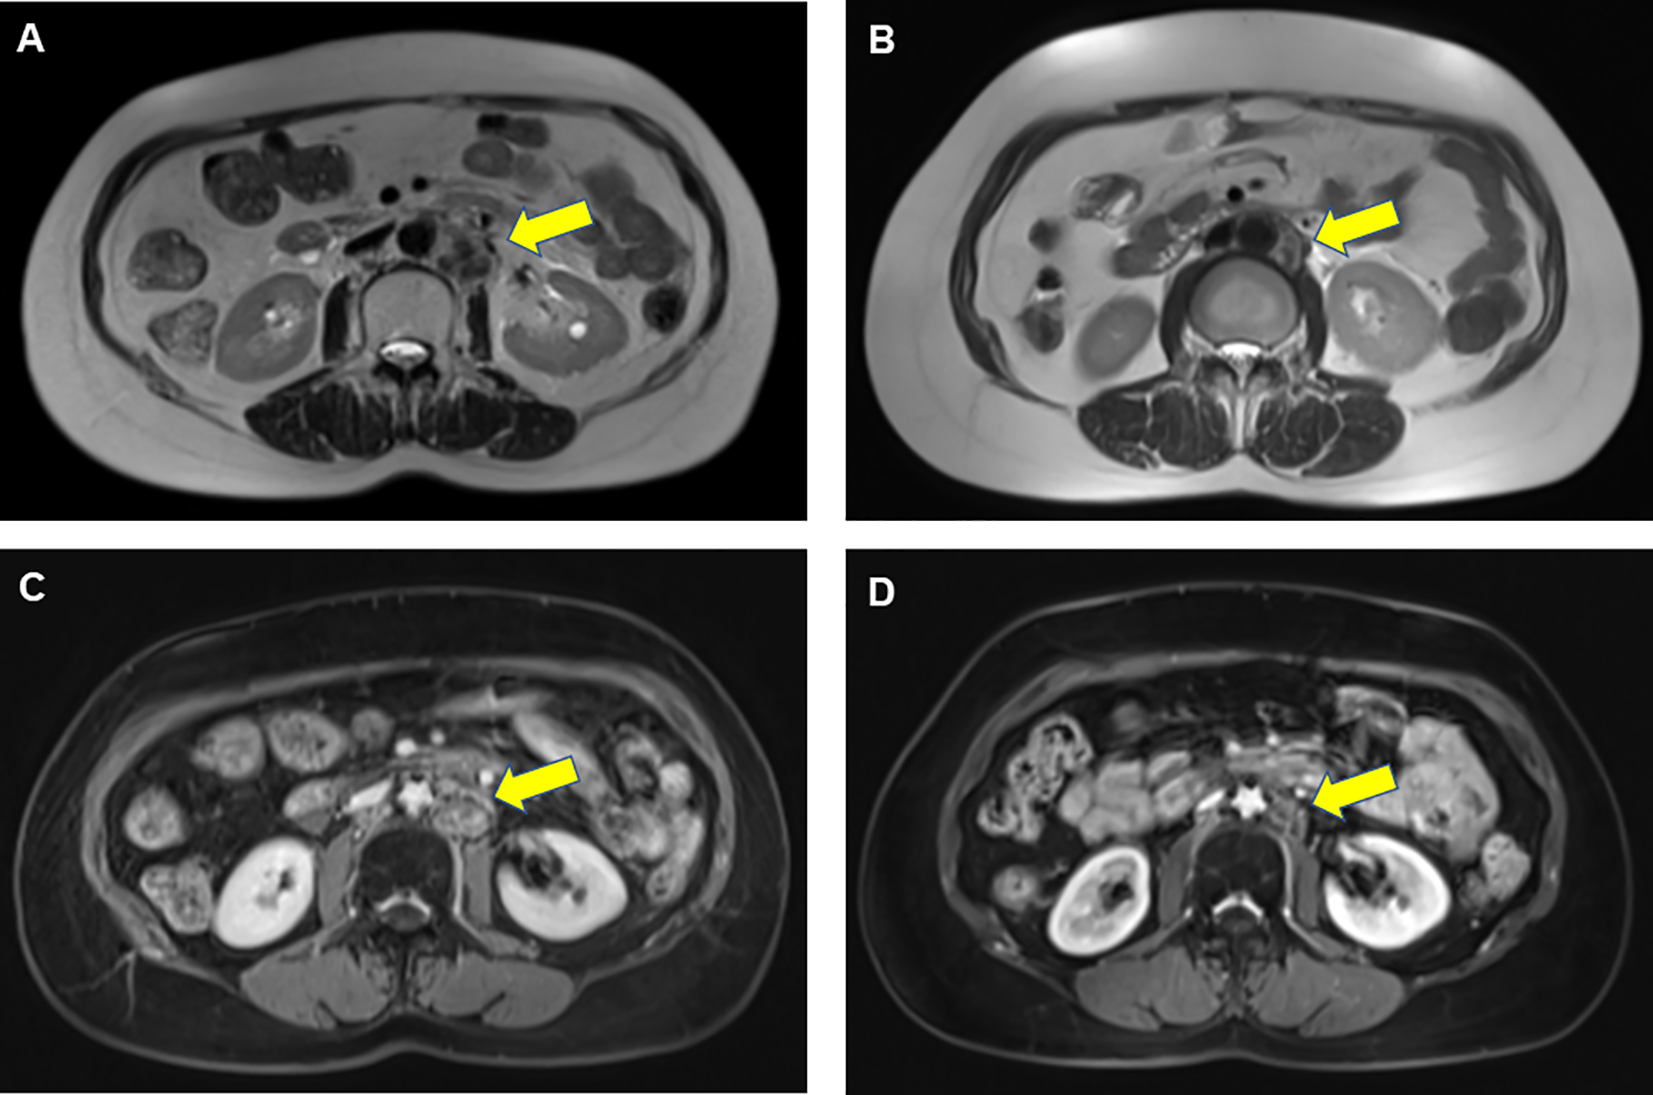

Given the benefit of previous immunotherapy, after a multi-disciplinary treatment (MDT) discussion and a thorough risk communication with the patient, she began treatment with Zimberelimab (240 mg, iv. Q3w), a novel fully humanized mAb to PD-1, from January 25, 2022, the tumor was in partial remission after 2 cycles of treatments (Figure 2), and the disease remained in continuous remission until our latest follow-up visit, September 14, 2022. Surprisingly, the patient did not experience any elevation of cardiac enzymes or symptoms related to myocarditis throughout the immunotherapy. The entire treatment history could be seen in Figure 3.

Figure 2

Results of abdominal MRI scans before and after ICI rechallenge treatment in a patient with endometrial cancer. Prior to PD-1 rechallenge, T2-weighted image (A) and T1-weighted enhanced scans (C) showed enlarged lymph nodes visible next to the abdominal aorta. After 2 cycles of PD-1 rechallenge, T2-weighted image (B) and T1-weighted enhanced sequence (D) indicated that those lymph nodes achieved partial remission. The yellow arrow represented tumor locations.